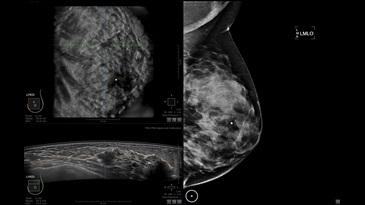

GE INVENIA ABUS – это современный УЗИ аппарат, который создан для точной и эффективной диагностики сканирования с высокой плотностью молочных желез. Выявляемость патологий раковых и предраковых стадий заболевания составляет 55%, что в конечном счете позволяет ставить врачу точные и своевременные диагнозы. Традиционные методы использования маммографии не показывают такой выявляемости, ограничиваясь лишь 3-38%.

УЗИ-аппарат GE INVENIA ABUS позволяет проводить максимально операторонезависимые процедуры, что значительно снижает риск неправильной постановки диагноза и сопутствующие издержки на обработку информации. Система готовит отчет в течение 3-х минут после сканирования, это безусловное преимущество по сравнению с обычным УЗИ сканером.

• Получение изображений в поперечной плоскости (в реальном времени) и в коронарной плоскости (статическая, для указания нахождения соска)

• Отображение объемных 3D ультразвуковых изображений, которые состоят из традиционных поперечных и воссозданных коронарных и сагиттальных проекций

• Стандартизованная ориентация изображения: «толстый срез» в коронарной плоскости; поперечная; сагиттальная плоскость; радиальный и антирадиальный поворот изображения; просмотр исключительно области интереса

• Одновременный просмотр двух изображений для сопоставления в коронарной плоскости